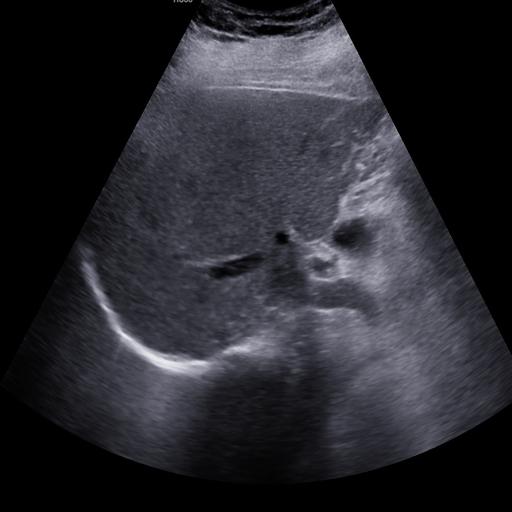

数据样例

正常肾脏样例

结石肾脏样例